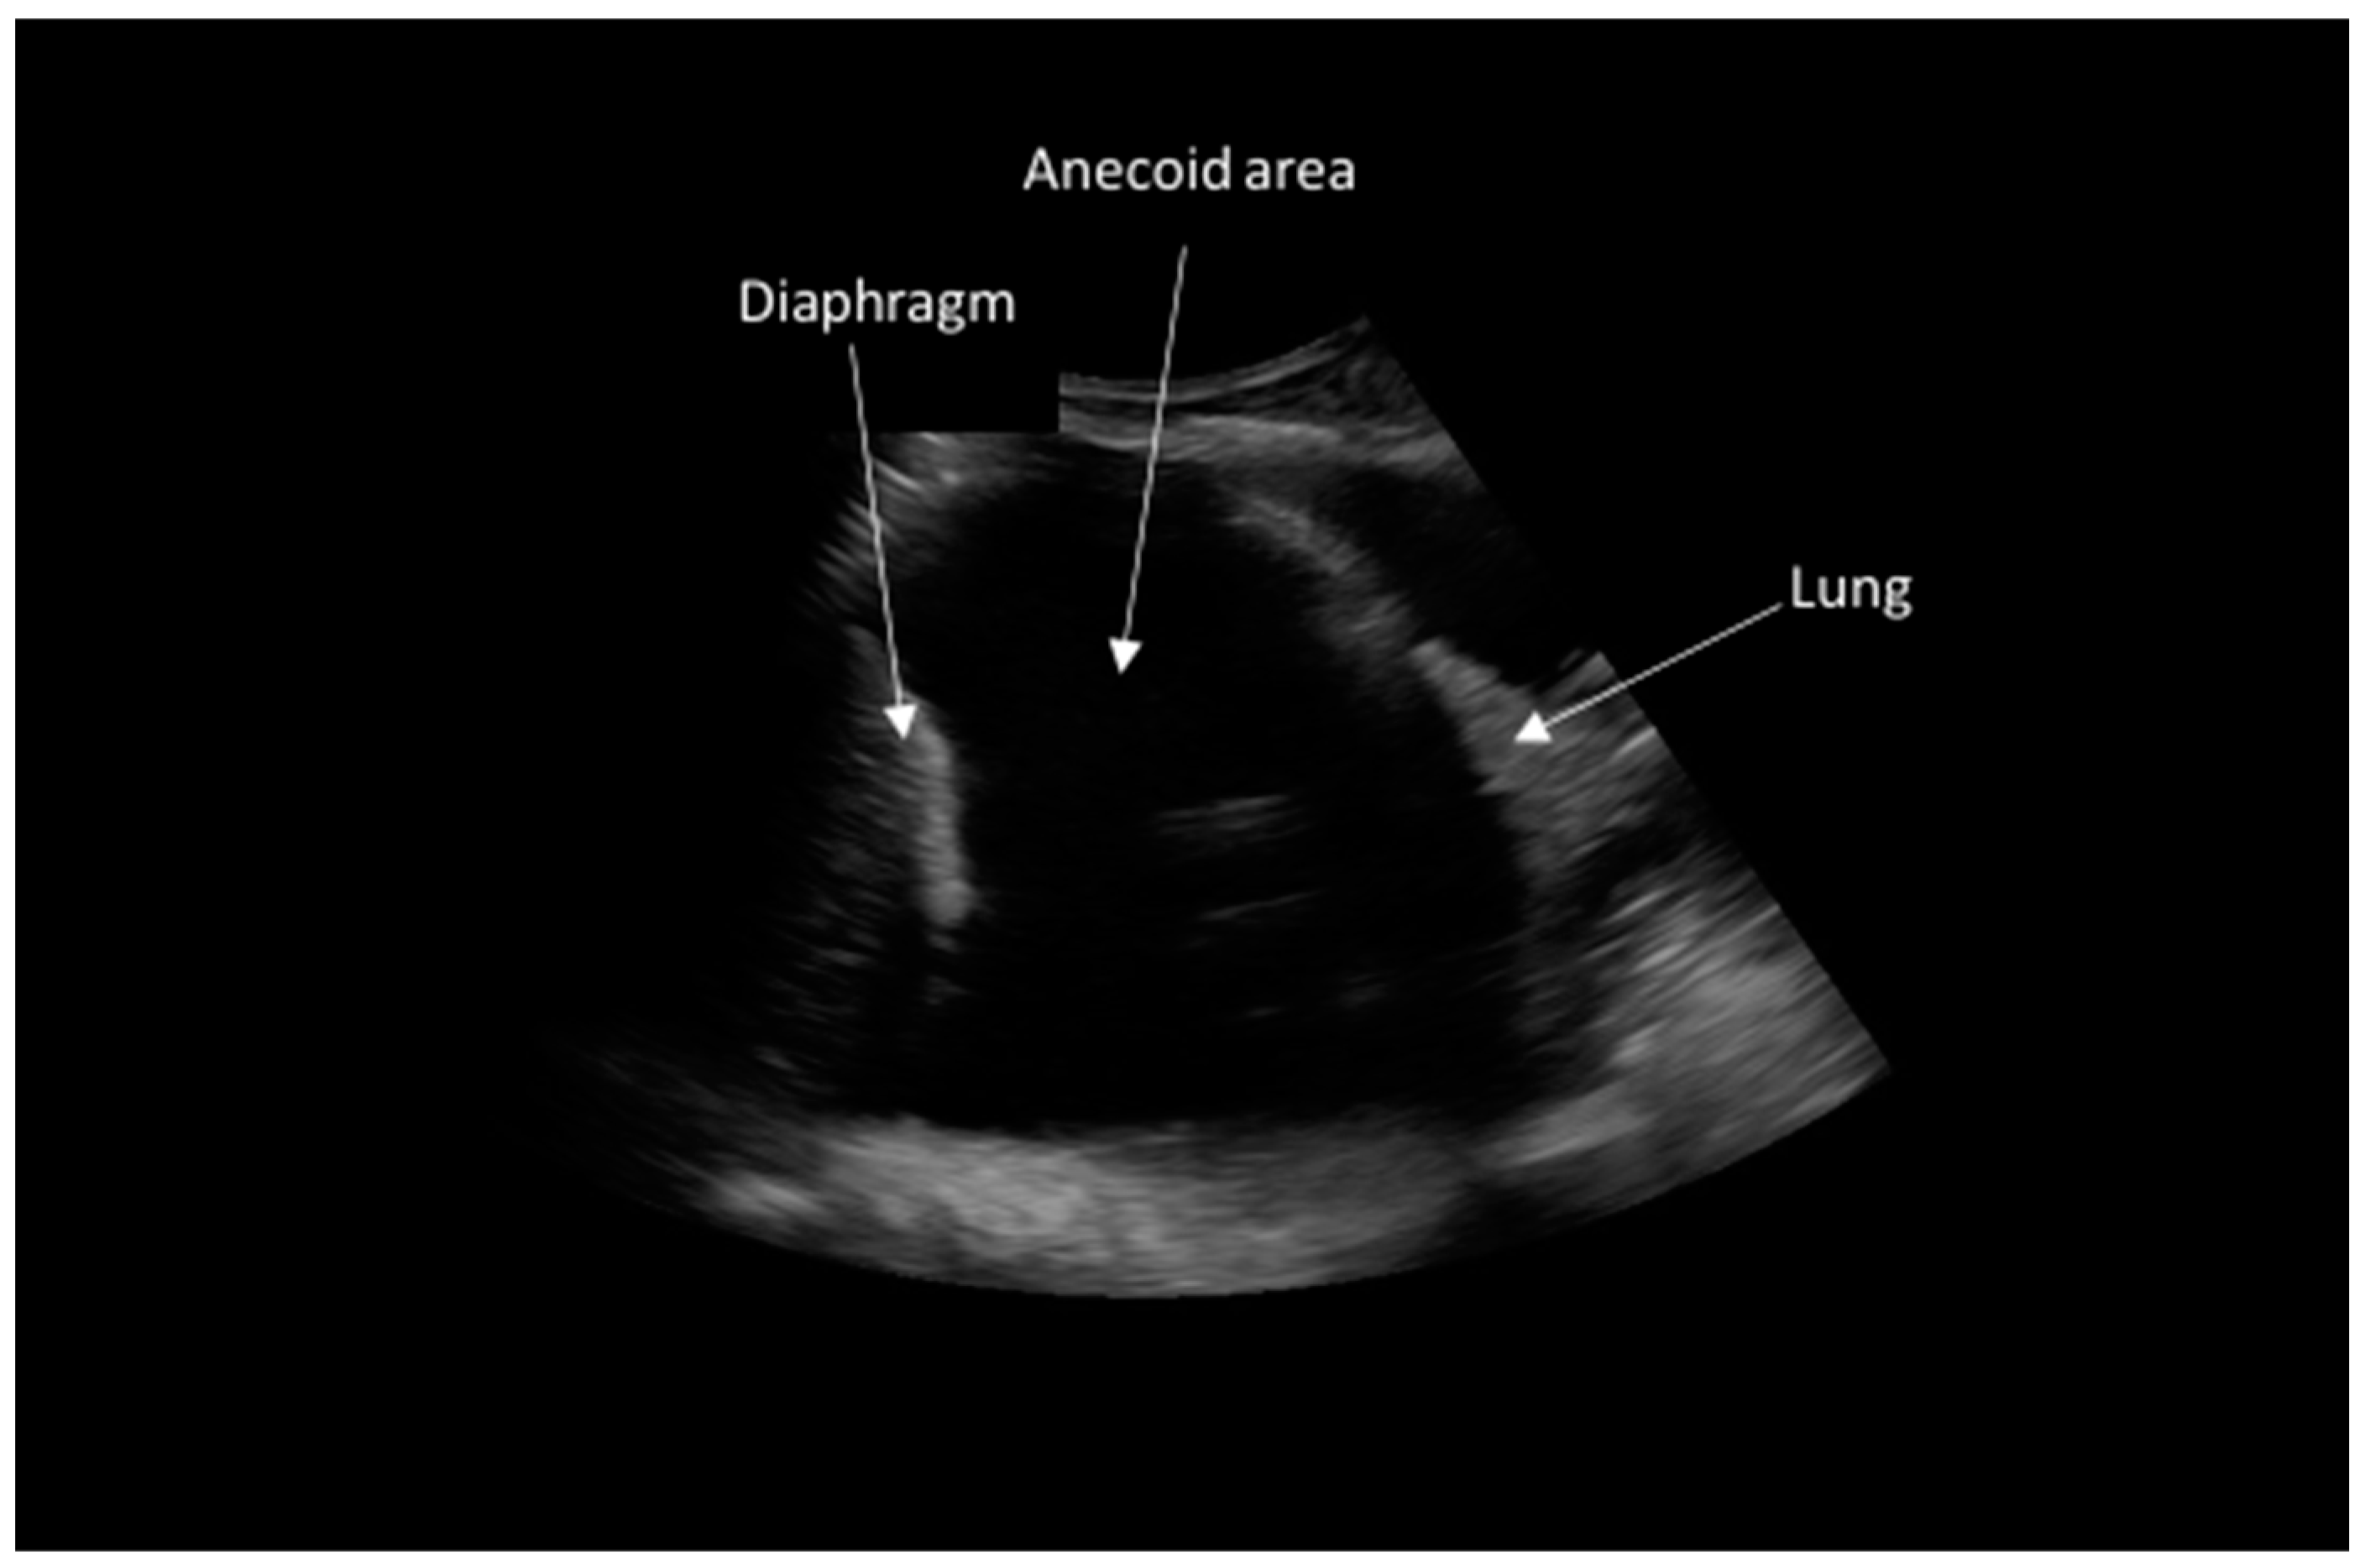

2.1. Diagnostic Imaging and Video-Assisted Thoracoscopic Surgery (VATS)